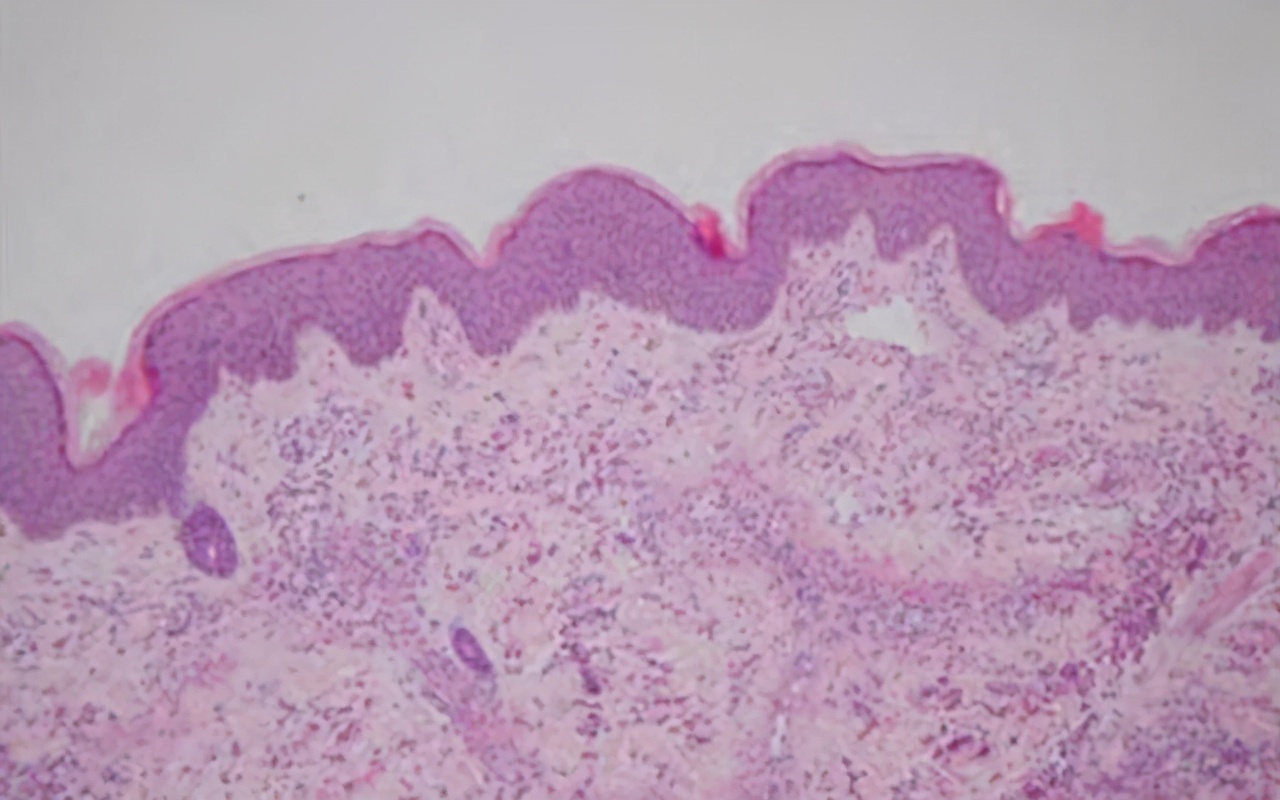

图片来源于网络,侵删

首先,过敏性紫癜本质上是一种血管炎疾病,机体出现红点红斑皮疹,说明病情已经复发,同时也说明过敏性紫癜没从根源治愈,也就是血液里的免疫复合物没有得到彻底清除,免疫紊乱情况依然还存在。也可以说明目前选择的治疗方式不得当。